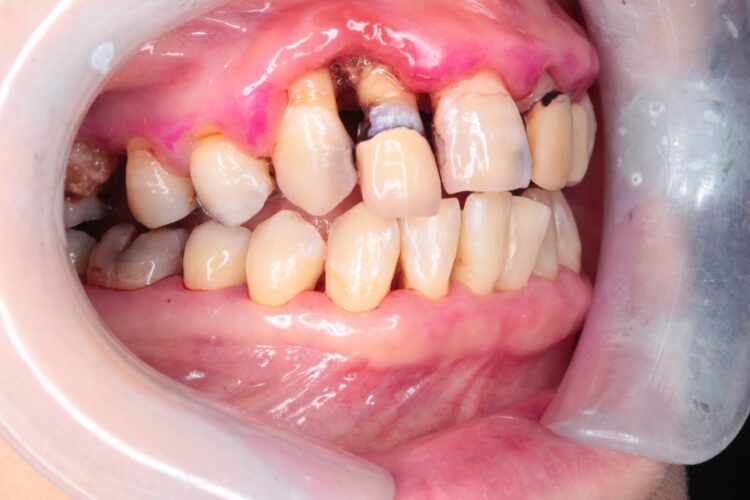

前回ご紹介した、歯周病治療を始められた方の続きです。

初診時と、本当の歯磨きを行ってから10日後の写真↓

だいぶ歯ぐきの腫れが治ってきていますね😊

歯ぐきが引き締まって歯周ポケットが浅くなったことで、

今まで歯周ポケット内に入っていた歯石も、少し見えるようになっています。

歯のすき間が以前より大きくなっているのが見えるでしょうか?

既に顎の骨が溶けて無くなっているので、病気を治すとすき間が開くことがあります。